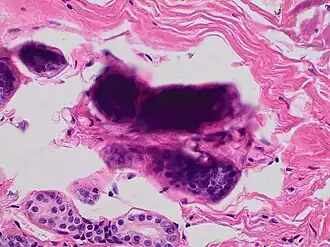

Staining artifacts by residual wax, resulting in pale areas where cellular structures are not discernible

Stacking of cells on top of each other gives a dark look, and in this breast tissue it may mimic microcalcifications.